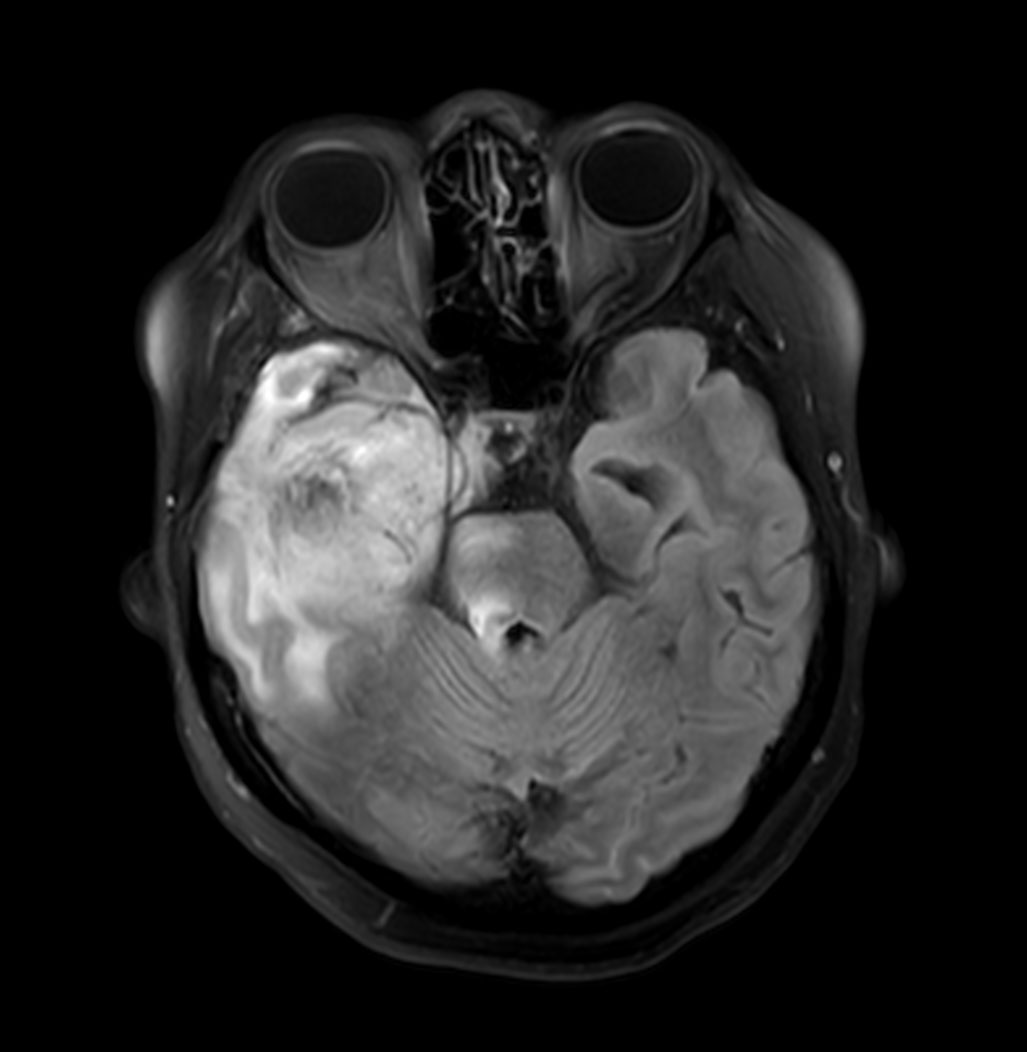

Axial T2w TSE

Patient with a history of astrocytoma. MRI scan requested post radiotherapy treatment. Diagnosis: Recurrent neoplastic disease.